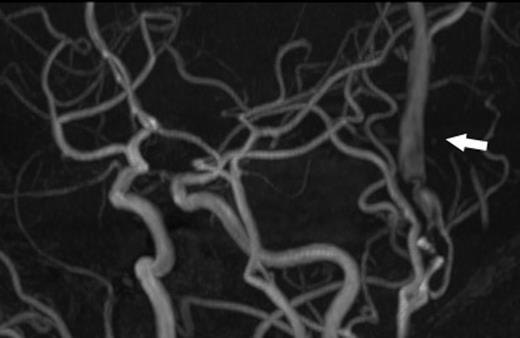

A 24-year-old male was admitted to our hospital after a traffic accident. Computed tomography scan had shown an acute epidural hematoma on the right surface of frontal lobe, which was emergently treated by surgical evacuation. One month later, he began to complain of pulsatile tinnitus in the left ear. A head magnetic resonance angiogram showed an extremely dilated vein in the left temporal region (Fig. 1). An angiography revealed a direct shunt between the left parietal branch of the STA and the superficial temporal vein (STV) in the preauricular region as well as an aneurysm in the left frontal branch of the STA (Fig. 2). He underwent surgery to remove the AVF and the aneurysm (Fig. 3). Pulsatile tinnitus disappeared immediately after surgery. Histopathological examination demonstrated that the artery was connected to the vein through the thin-walled vessels lacking internal elastic lamina and muscularized media, suggesting that the connecting vessels were newly formed (Fig. 4).

A magnetic resonance angiogram showed the dilated STV (arrow).